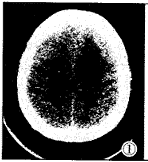

CT表现:脑脓肿的形成经历3个阶段,即化脓性脑炎阶段、化脓阶段和脓肿壁形成阶段 [2]。但CT表现多为2个阶段,因化脓和脓肿壁形成合二为一个阶段。感染开始,局部脑组织炎性浸润、软化、坏死,即化脓性脑炎阶段;接着脑质软化、坏死区逐渐扩大,形成脓腔,最后脓腔周围形成完整的脓肿壁,即化脓和脓肿壁形成阶段。CT检查不但能提高脓肿的检出率和诊断的准确性,而且可导向引流和判断疗效,对临床治疗有指导意义。CT阶段表现:①脑炎阶段:2例,均为女性。1例表现为右顶叶约2.5cm×2.0cm范围低密度区,边界不清、模糊,CT值较正常脑组织低10~15HU。另1例表现为双侧顶叶后部皮质区有片状低密度区,增强无强化(图1)。②化脓和脓肿壁形成阶段:3例,表现为灰质或白质区的大片低密度区,边界模糊,增强后见有环形强化,壁厚3~5mm,壁光滑、均匀,无结节、无子灶,周围有脑水肿及脑回样强化,水肿广泛者脑室及中线结构受压、移位(图2)。

图1 平扫,左侧半卵园形中心髓质部事边界模糊的低密度区,中线结构无移位。 图2 增强扫描(与图1系同一病人),12天后增强扫描,左侧半卵园中心髓质内见环状强化灶,中心密度低,周围水肿,有占位效应,中线结构右移位 。